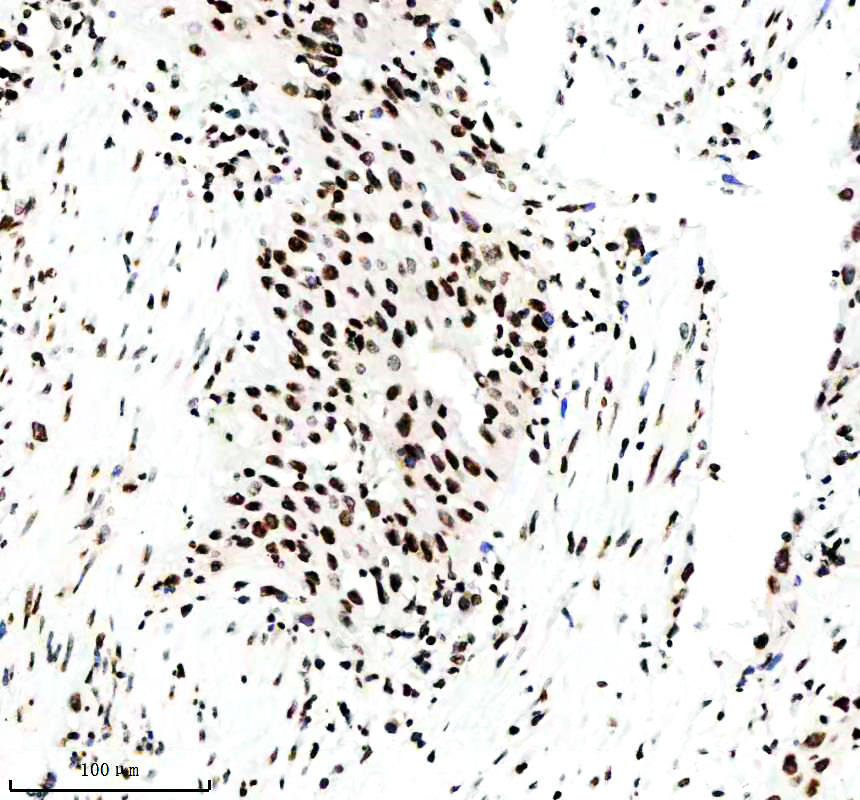

IHC analysis of Histone H3 (acetyl K14) using anti-Histone H3 (acetyl K14) antibody (BM4151) .

Histone H3 (acetyl K14) was detected in a paraffin-embedded section of human lymphoma tissue. The tissue section was incubated with rabbit anti-Histone H3 (acetyl K14) Antibody (BM4151) at a dilution of 1:200 and developed using HRP Conjugated Rabbit IgG Super Vision Assay Kit (Catalog # SV0002) with DAB (Catalog # AR1027) as the chromogen.